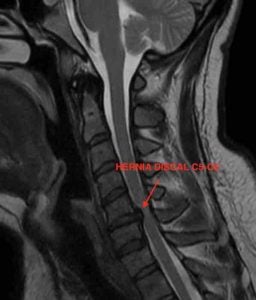

RMN Columna Cervical: Cambios postquirúrgicos con material de fijación. Hernia discal C5-C6.

Hernia discal C5-C6, material de fijación C6-C7

Paciente presenta síndrome de nivel adyacente, es decir el disco inmediato superior a la cirugía previa se lesiona produciéndose la hernia discal. Tras las pruebas se decide reintervenir al paciente. En este caso consideramos que la artrodesis percutánea de columna cervical con D-TRAX es la mejor opción quirúrgica. Al abordar el problema por vía posterior evitamos la fibrosis de la primera cirugía. También evitamos la posibilidad de lesionar estructuras nerviosas importantes. Además la recuperación del paciente será más rápida.